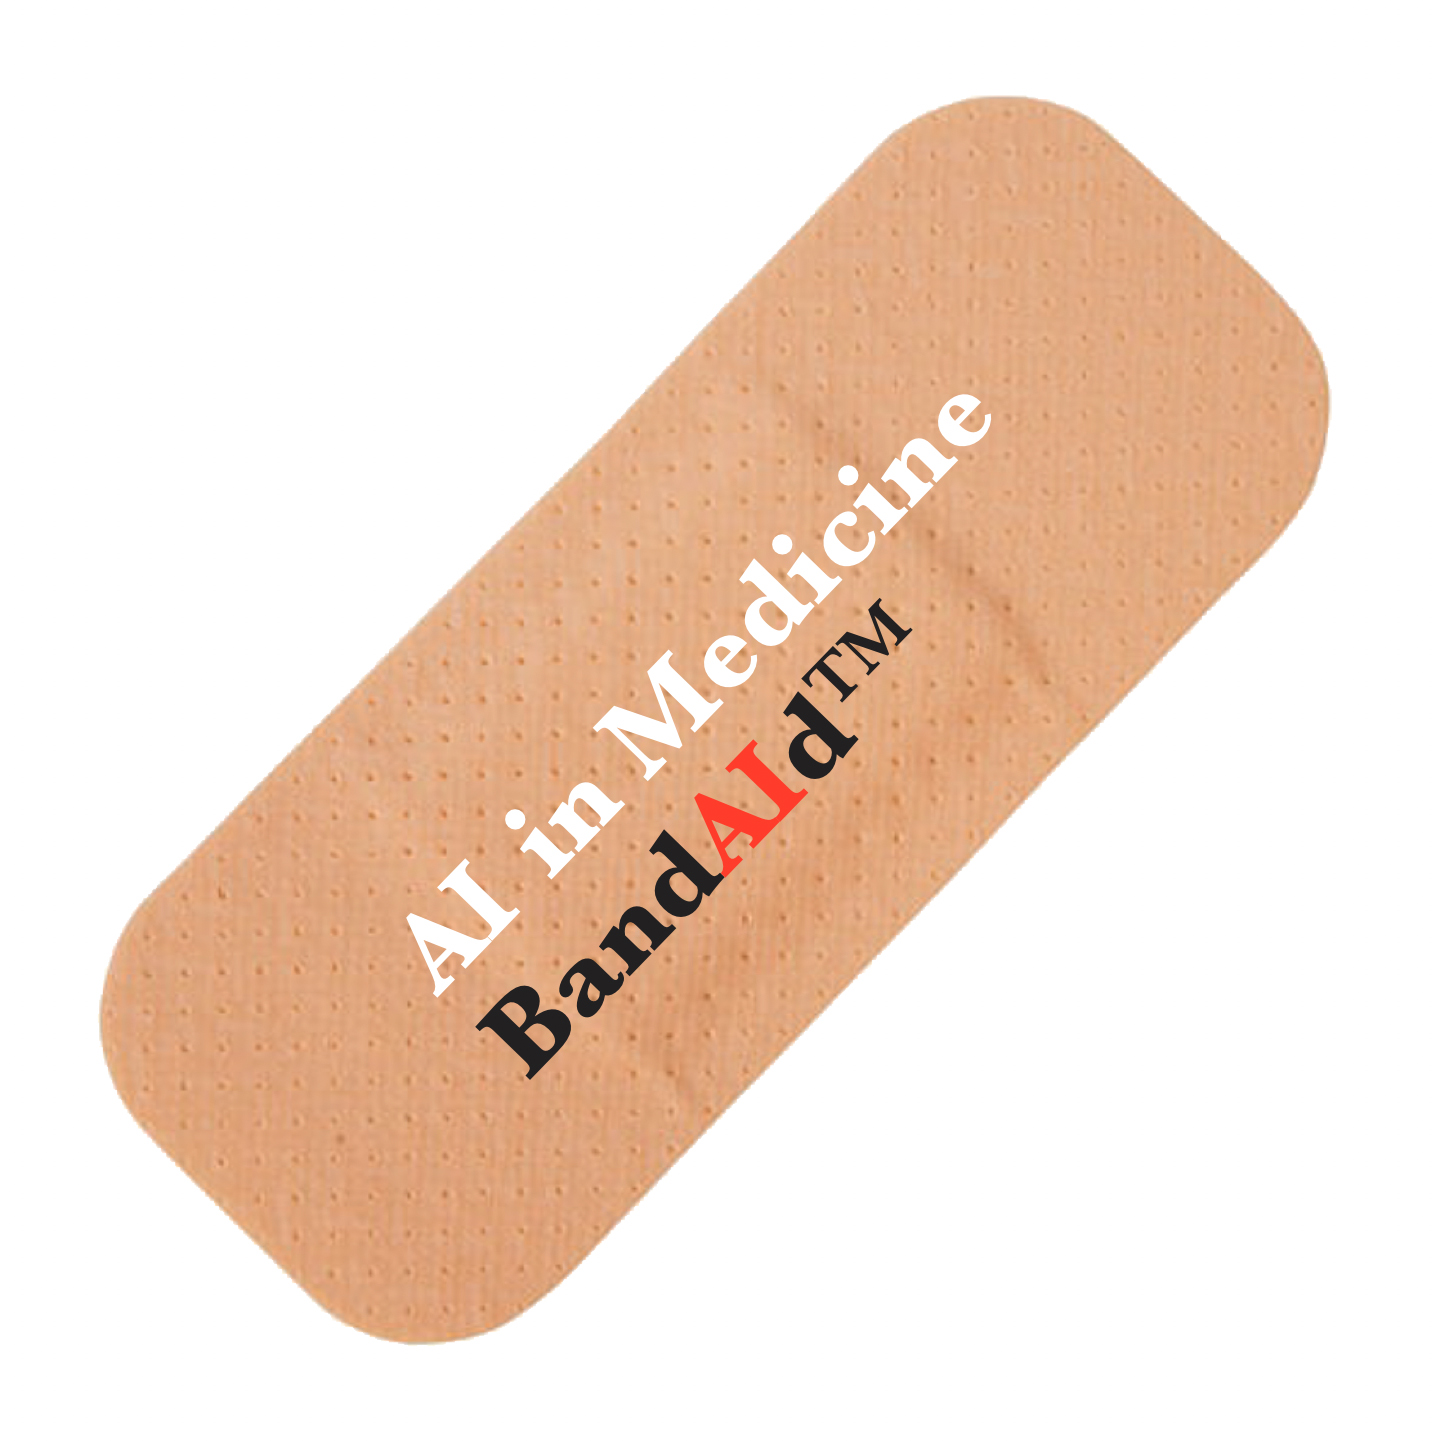

A company Professor Webster is involved in has developed a breathalyser that can detect analytes in one’s breath to diagnose everything from Alzheimer’s disease, infections, sexually transmitted diseases, COVID-19, and more (Figure 2). Quarksen is revolutionising sensor use and has thus made it possible to easily track disease treatment through individuals’ breath. They are incorporating AI algorithms to interpret data collected from such breathalysers and predict better treatments.